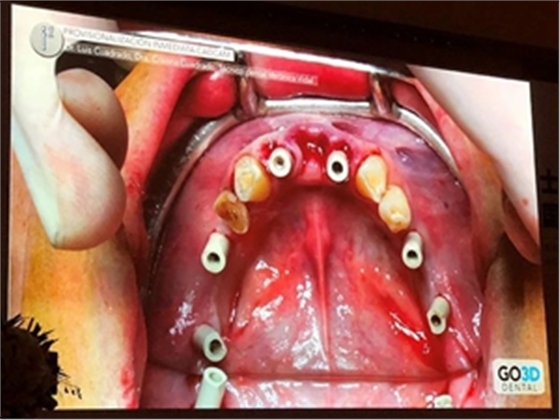

在Dr. Luis Cuadrado的全數(shù)字化修復(fù)流程中,因不需取傳統(tǒng)模型而更為高效精準(zhǔn)。Dr. Luis Cuadrado通過病例展示了他的標(biāo)準(zhǔn)步驟:

第一,使用口掃設(shè)備對(duì)患者掃描,制取數(shù)字化研究模型。

第二,拔除余留牙。Dr. Luis Cuadrado建議此時(shí)保留至少兩顆患者天然牙以作為掃描參考點(diǎn)。

第三,植入種植體,安裝掃描桿,并再次進(jìn)行口內(nèi)掃描,獲取數(shù)字化植入信息。

第四,技工中心可以籍由植入前后天然牙為參考點(diǎn),在軟件上將兩次數(shù)字化印模進(jìn)行精準(zhǔn)結(jié)合,從而制作與患者術(shù)前咬合關(guān)系一致的臨時(shí)義齒。